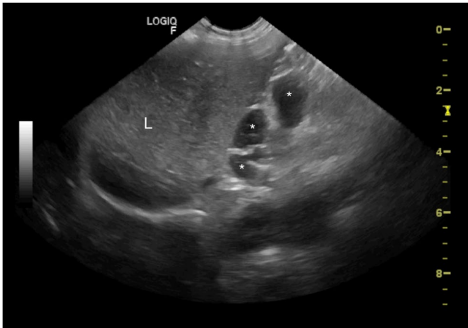

本刊推荐:针对犬类全身性淋巴结病变易误诊为淋巴瘤的问题,研究人员通过一例迷你雪纳瑞犬的临床案例,开展鸟分枝杆菌复合体(MAC)感染模拟恶性肿瘤的鉴别诊断研究。通过细胞学染色、分子鉴定(GenoType Mycobacterium CM)及药敏测试,确诊MAC感染并调整治疗方案(克拉霉素替代利福平)。结果强调齐尔-尼尔森染色在细胞学检查中的关键作用,揭示迷你雪纳瑞犬可能存在CARD9基因相关的免疫缺陷易感性。该研究为罕见人兽共患病的精准诊疗提供重要参考,发表于《BMC Veterinary Research》。